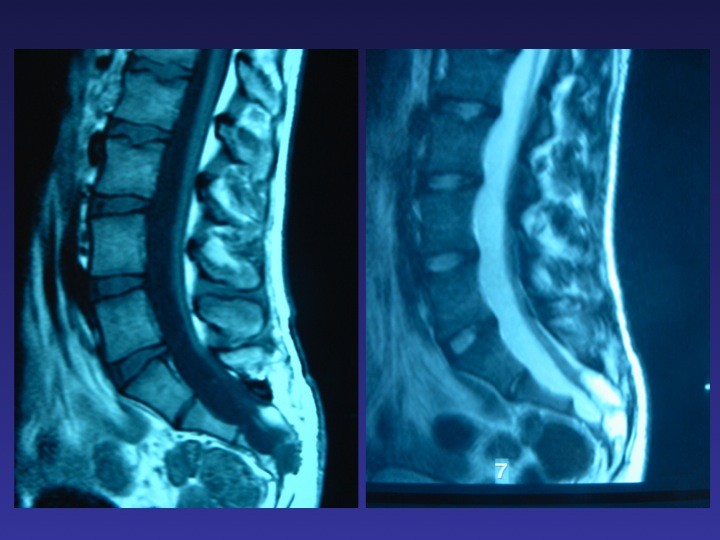

TABLE RONDE – La moelle attachée de l’enfant et de l’adolescent : diaporama 1

TABLE RONDE – La moelle attachée de l’enfant et de l’adolescent : diaporama 2